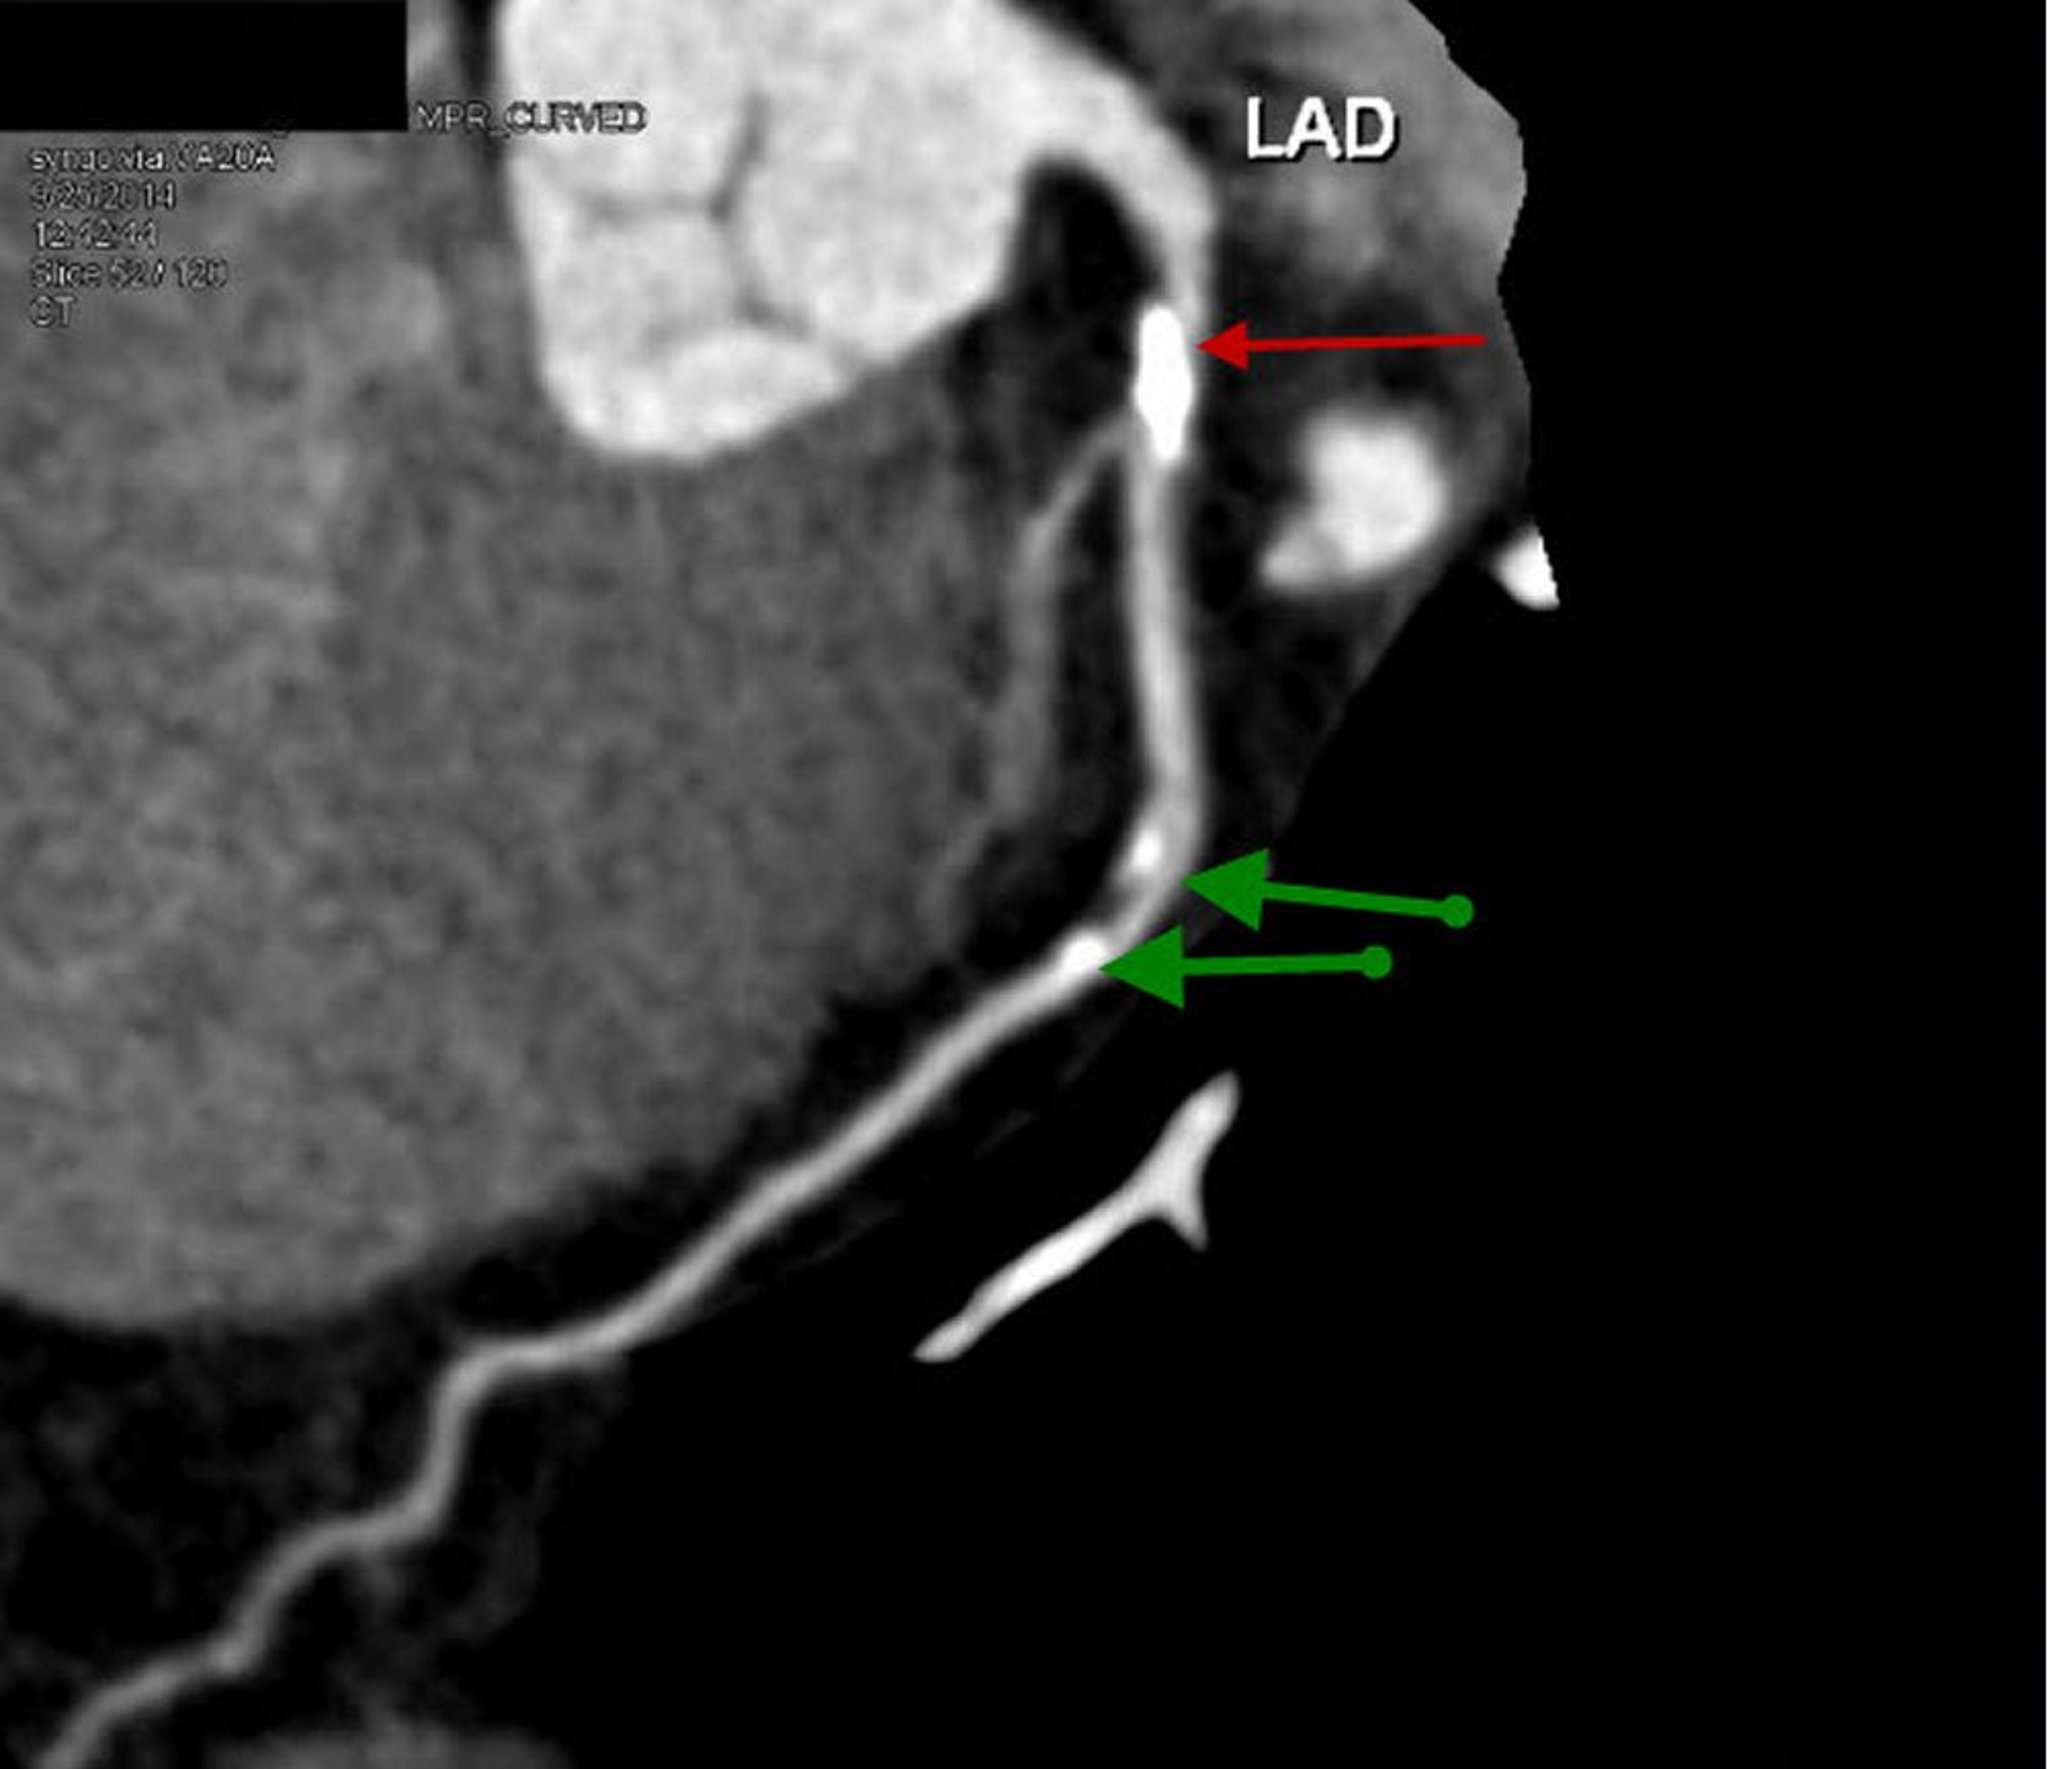

TC com contraste mostrando doença arterial coronariana

Essa TC com contraste mostra uma incidência sagital reconstruída da artéria descendente anterior esquerda proximal com placa calcificada proeminente e 70% de estenose (seta vermelha). DAE leve mostra estenose leve de 20% a 30% (setas verdes).